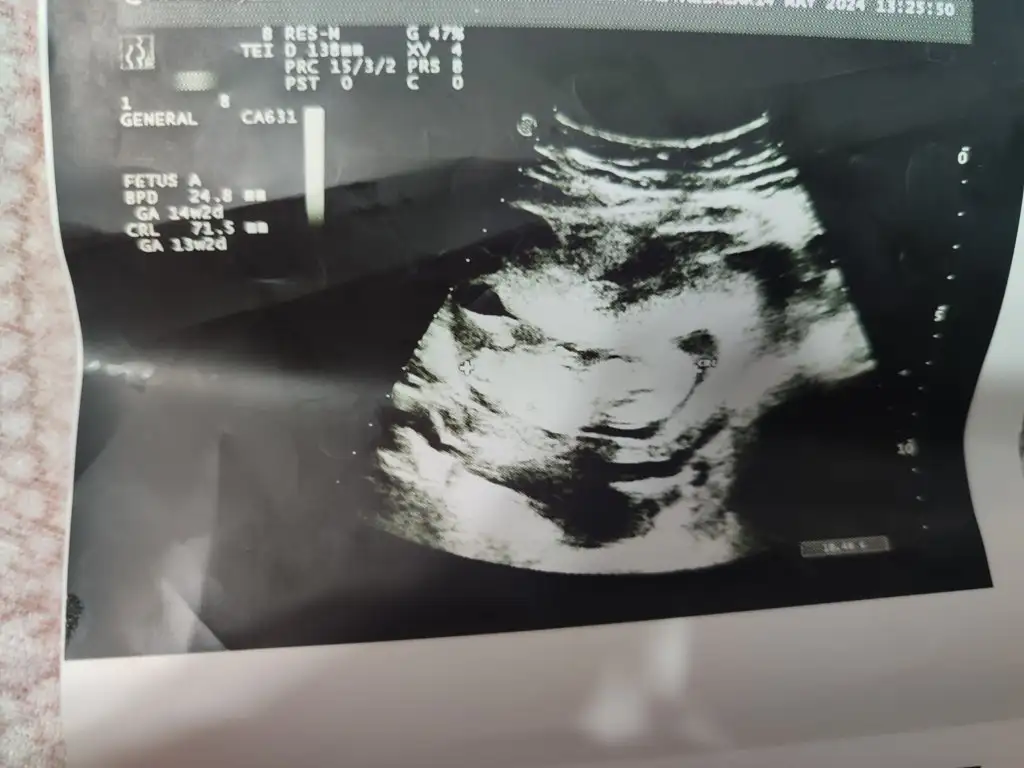

İyi günler tahmini olan varmı